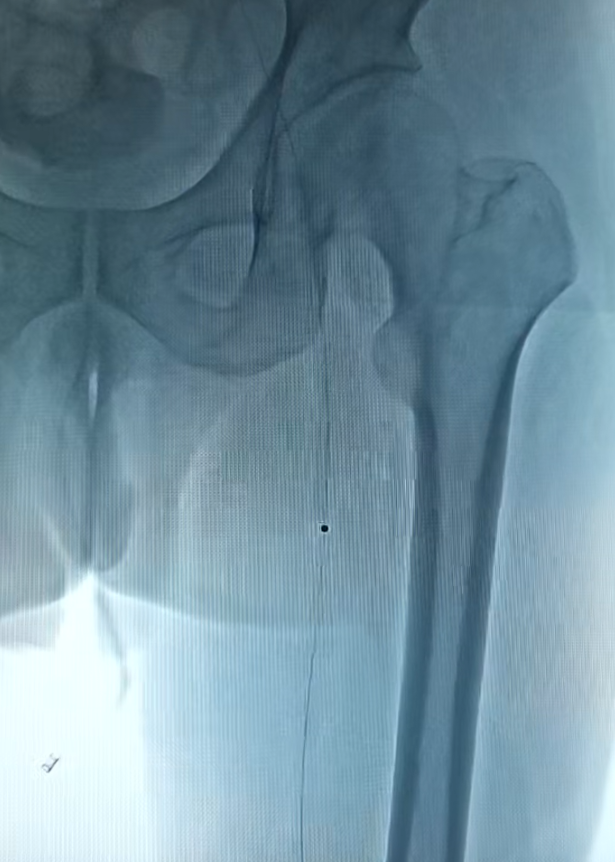

足部动脉的术前(左)术后(右)影像对比

在激光成功“开路”后,团队再辅以必要的球囊扩张,最终实现血管的完美重建。术后复查显示,患者下肢血流恢复通畅、疼痛消失,保肢成功,生活质量得到根本性改善。